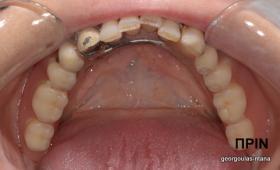

ΟΛΙΚΗ ΑΠΟΚΑΤΑΣΤΑΣΗ ΑΝΩ Κ ΚΑΤΩ ΓΝΑΘΟΥ ΜΕ ΕΜΦΥΤΕΥΜΑΤΑ, ΑΜΕΣΗ ΦΟΡΤΙΣΗ Κ ΑΝΟΙΚΤΗ ΑΝΥΨΩΣΗ ΙΓΜΟΡΕΙΟΥ

Η ασθενής αυτή είχε παλιές ακίνητες αποκαταστάσεις (γέφυρες) στην άνω γνάθο  κ μια κινητή προσθετική αποκατάσταση (μερική οδοντοστοιχία-"μασελάκι") στην κάτω γνάθο. Ήταν δυσαρεστημένη τόσο με την εμφάνιση όσο και με τη λειτουργία των δοντιών της καθώς παραπονιόταν ότι  είχαν εντονη κινητικότητα ενώ και οι προσθετικές τους εργασιές δεν ήταν σταθερές. Η πρόγνωση των δοντιών κρίθηκε φτωχή με αποτέλεσμα να μην είναι δυνατή η συμμετοχή τους σε μια νεα προσθετική αποκατάσταση με μακροχρόνια διάρκεια. Η ασθενής επιθυμούσε οι νέες αποκαταστάσεις να είναι σταθερές και ακίνητες.  Για το λόγο αυτό αποφασίστηκε η ολική αποκατάσταση της άνω κ κάτω γνάθου με ακίνητες επιεμφυτευματικές εργασίες. Στην αριστερή πλευρά της άνω γνάθου, λόγω μη επαρκούς οστού για την τοποθέτηση εμφυτευμάτων προηγήθηκε επέμβαση ανοιχτής  ανύψωσης ιγμορείου άντρου με τη χρήση πιεζοχειρουργικού μηχανήματος ώστε να δημιουργηθεί το κατάλληλο οστικό υπόστρωμα. Ακολούθησε σε επόμενο χειρουργείο η εξαγωγή των υπάρχοντων δοντιών κ η άμεση τοποθέτηση εμφυτεύματων (άμεση εμφύτευση) κ δύο μέρες μετά η τοποθέτηση προσωρινής εργασίας επί των εμφυτευμάτων (άμεση φόρτιση) με αποτέλεσμα η ασθενής να μη μείνει καθόλου χωρίς δόντια κ να είναι καλυμένη αισθητικά όσο καιρό διήρκησε η εργασία